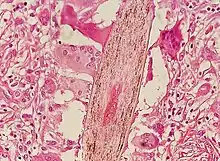

Folliculitis is infection or inflammation of one or more hair follicles resulting in one or more small pustules or red bumps.[1] These are generally tender and may be itchy.[2] The condition may occur anywhere on hair covered skin.[1][3] Complications include cellulitis or abscess.[1]